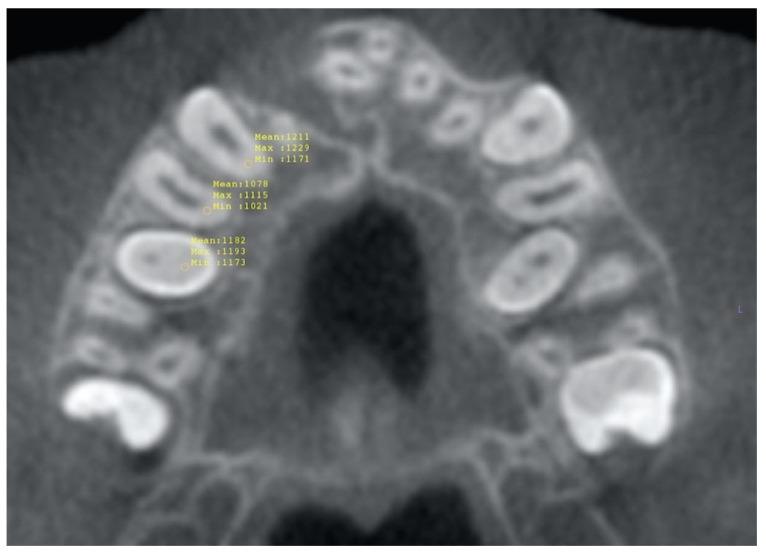

In children born with cleft lip and palate, the timing of the secondary alveolar bone graft (SABG) is crucial to its success; this involves estimating the eruption of the permanent maxillary canine. Altered dental eruption in this patient group gives impetus to the identification of dental developmental factors concerning maxillary canine eruption, which may steer the clinical decision of SABG timing. Records of over nine hundred patients who received SABG with pre- and post-operative cone beam computed tomography (CBCT) scans were analyzed for inclusion and divided into two groups (erupting or non-erupting canine after SABG). Roots of the maxillary canines and premolars were segmented from the cementoenamel junction then linear and volumetric measurements were performed. The pre- and post-operative root length and volume differences were calculated and compared statistically using independent sample tests and paired -tests. No statistically significant differences were found in the volume change (%), or reciprocal of mean root length in the erupted and unerupted groups in the canine, first premolar, or second premolar roots except for an association between the post-operative dental root length of the canine and the maxillary canine eruption status. Therefore, assessment of root development from pre-treatment CBCT scans was not deemed worthy from a diagnostic perspective.